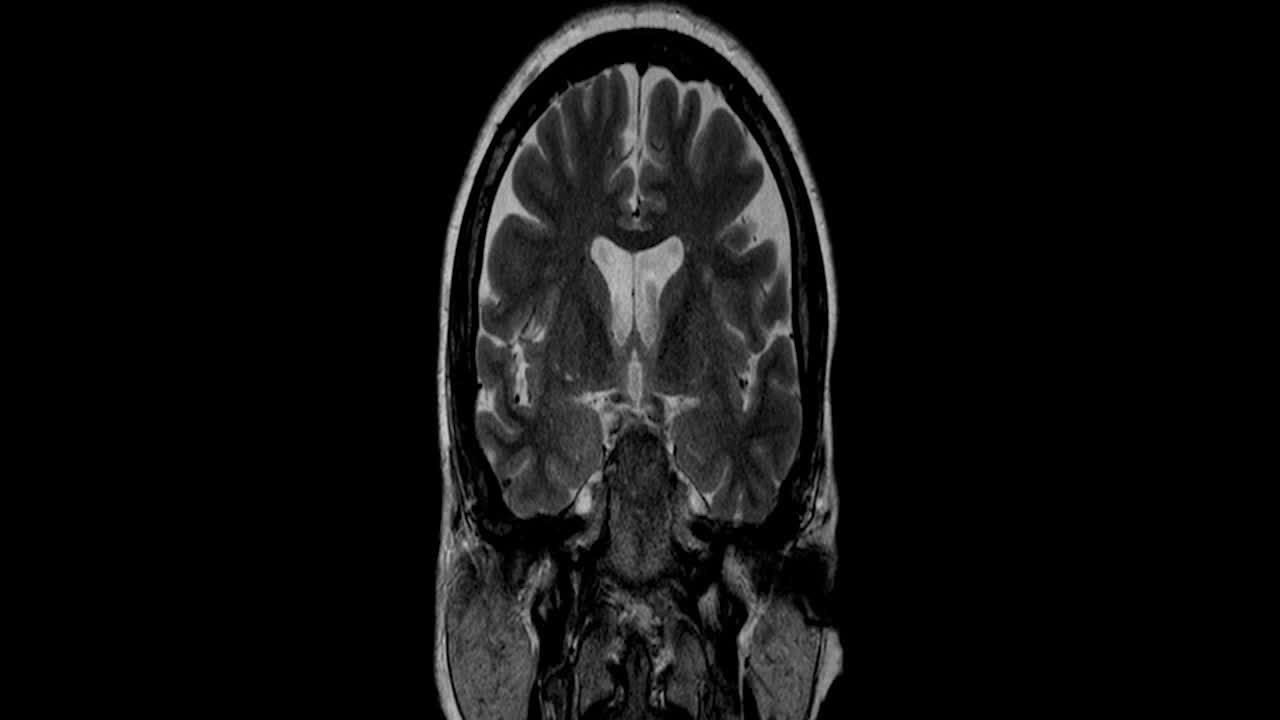

Parkinson's disease is a progressive movement disorder of the nervous system, according to the National Institute of Neurological Disorders and Stroke. It happens when nerve cells, or neurons, in parts of the brain responsible for producing dopamine weaken, become damaged, or die. Dopamine is not only known as the "feel-good" chemical but is also a neurotransmitter that allows the body to move. Without enough dopamine, a person may experience tremors, fatigue, slow movement, speech difficulties, falls, and other symptoms. This condition typically worsens over time.